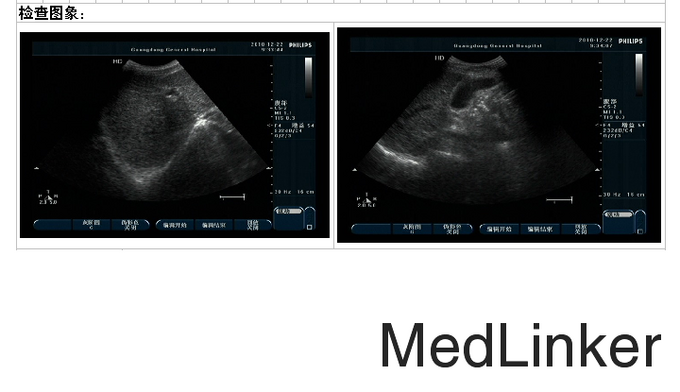

轻度贫血貌,无肝掌,胸前可见蜘蛛痣,双肺听诊呈清音。心率68次/分,心律齐,未闻及病理性杂音。腹平坦,无腹壁静脉曲张,移动性浊音阳性。双下肢轻度凹陷性水肿。 血常规正常; 电解质:镁 0.67mmol/L ↓;钾 3.44mmol/L ↓; 血脂分析:甘油三酯 0.44mmol/L ↓;总胆固醇 3.98mmol/L ;低密度脂蛋白 2.21mmol/L ↓;高密度脂蛋白 0.78mmol/L ↓; 肝功:丙氨酸氨基转移酶 34U/L ;碱性磷酸酯酶 86U/L ;胆碱酯酶 3882U/L ↓;门冬氨酸氨基转移酶 51U/L ↑;总胆红素 33.8umol/L ↑;白蛋白 32.7g/L ↓;结合胆红素 6.9umol/L ; 肾功:尿酸 376umol/L ;肌酐 81umol/L ; 肿瘤指标正常; 乙肝两对半定量:乙肝核心抗体定量 0.006COI ↑;乙肝e抗体定量 0.019COI ↑;乙肝e抗原定量 0.127COI ;乙肝表面抗体定量 2IU/L ;乙肝表面抗原定量 3912COI ↑; 乙型肝炎病毒核酸扩增荧光定量:HBV-DNA定量 <500IU/ml ; 凝血指标正常; 肝胆胰脾螺旋CT平扫+增强:肝硬化,门静脉高压侧支循环形成,脾大,腹水;拟胆囊炎;右肺中叶少许慢性感染灶;主动脉粥样硬化。 胃镜:1.食管静脉曲张(中-重度) 2.慢性浅表性胃炎伴糜烂 。 腹部B超:1、肝硬化、门脉高压(门静脉增宽并血流速度减低、脾静脉增宽、胆囊壁水肿、脾大、腹盆腔积液);2、胰腺未见明显异常。